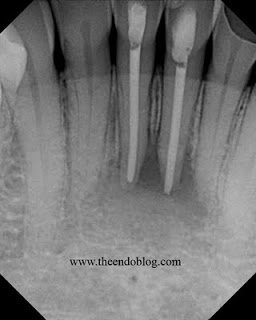

The following case is a similar, double apicoectomy. The CBCT confirmed that there were no missed canals. The large posts and good crown margins were the reasons we chose surgery over non-surgical retreatment.